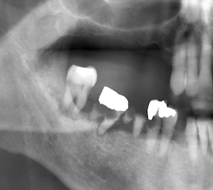

超过10000个临床病例,取得了非常好的效果

已顺利完成临床试验,预计将于2025年二季度获得三类医疗器械证书